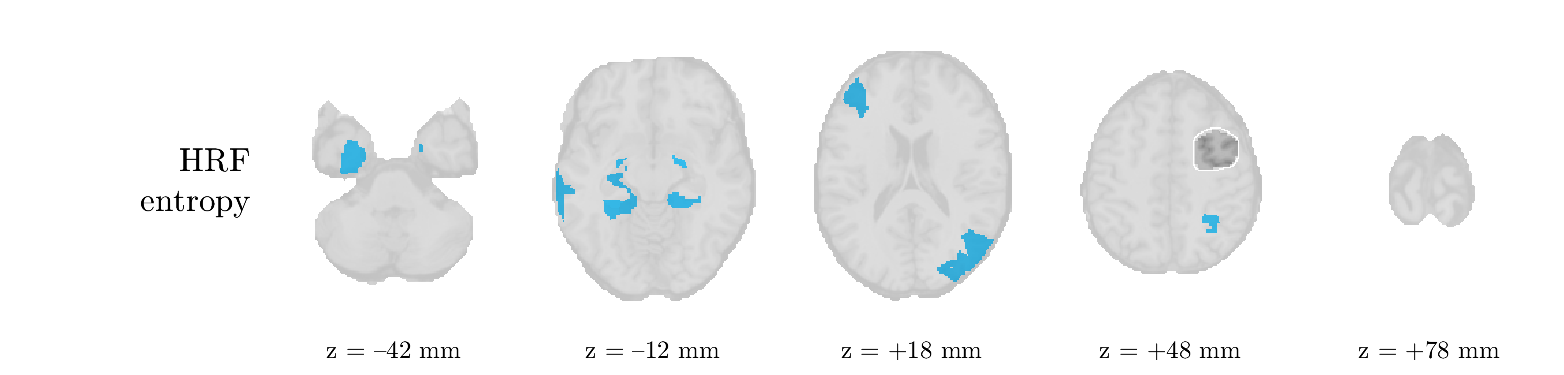

Patient 1

We analyze the solution with sources. Figure 1 shows the EEG signatures and HRF waveforms. One of the sources is highly correlated to the MWF reference (in grey), which was already known from Table B.3. This IED-related source had a typical low-frequency spectrum, which is expected for the typical spike-and-wave interictal discharges. The topography is relatively diffuse, although the highest amplitudes are mostly in the left hemisphere. This is in accordance with the lateralization of ictal onset zone (left temporal lobe, cfr. Table 1). There are some noteworthy observations to be made about some of the other components. The fourth has an unusually sharp spectrum, is mainly localized on two nonadjacent center electrodes, and is sustained for a single period of many seconds Hence, this component likely captured an artifact (of yet unknown origin), although we spotted no large-amplitude changes in the EEG itself. Similarly, the third source is only present at one frontal electrode, and exists in a frequency range above 20 Hz. It might represent a muscle artifact, e.g., due to frowning or twitching of some muscles in the forehead. The HRFs of all ROIs are shown in Figure 1(b). Two of the basis functions seem to have converged to a very similar waveform, which is an unfortunate possibility if two initial HRFs are too close to the same local optimum in their respective parameters. This reduces the expressive power of the basis set, which is clearly visible, since many ROIs have a nearly identical HRF. One of the twenty ROIs with the highest-entropy HRF overlapped the IOZ, although clearly this HRF (bold line) is not among the most dissimilar waveforms for this patient. This is also visible in Figure 2: both the HRF entropy and extremity maps show a small overlap with the delineated IOZ. Despite the good correspondence in the EEG domain, no significant (de)activation of the IED-component is found inside the IOZ.